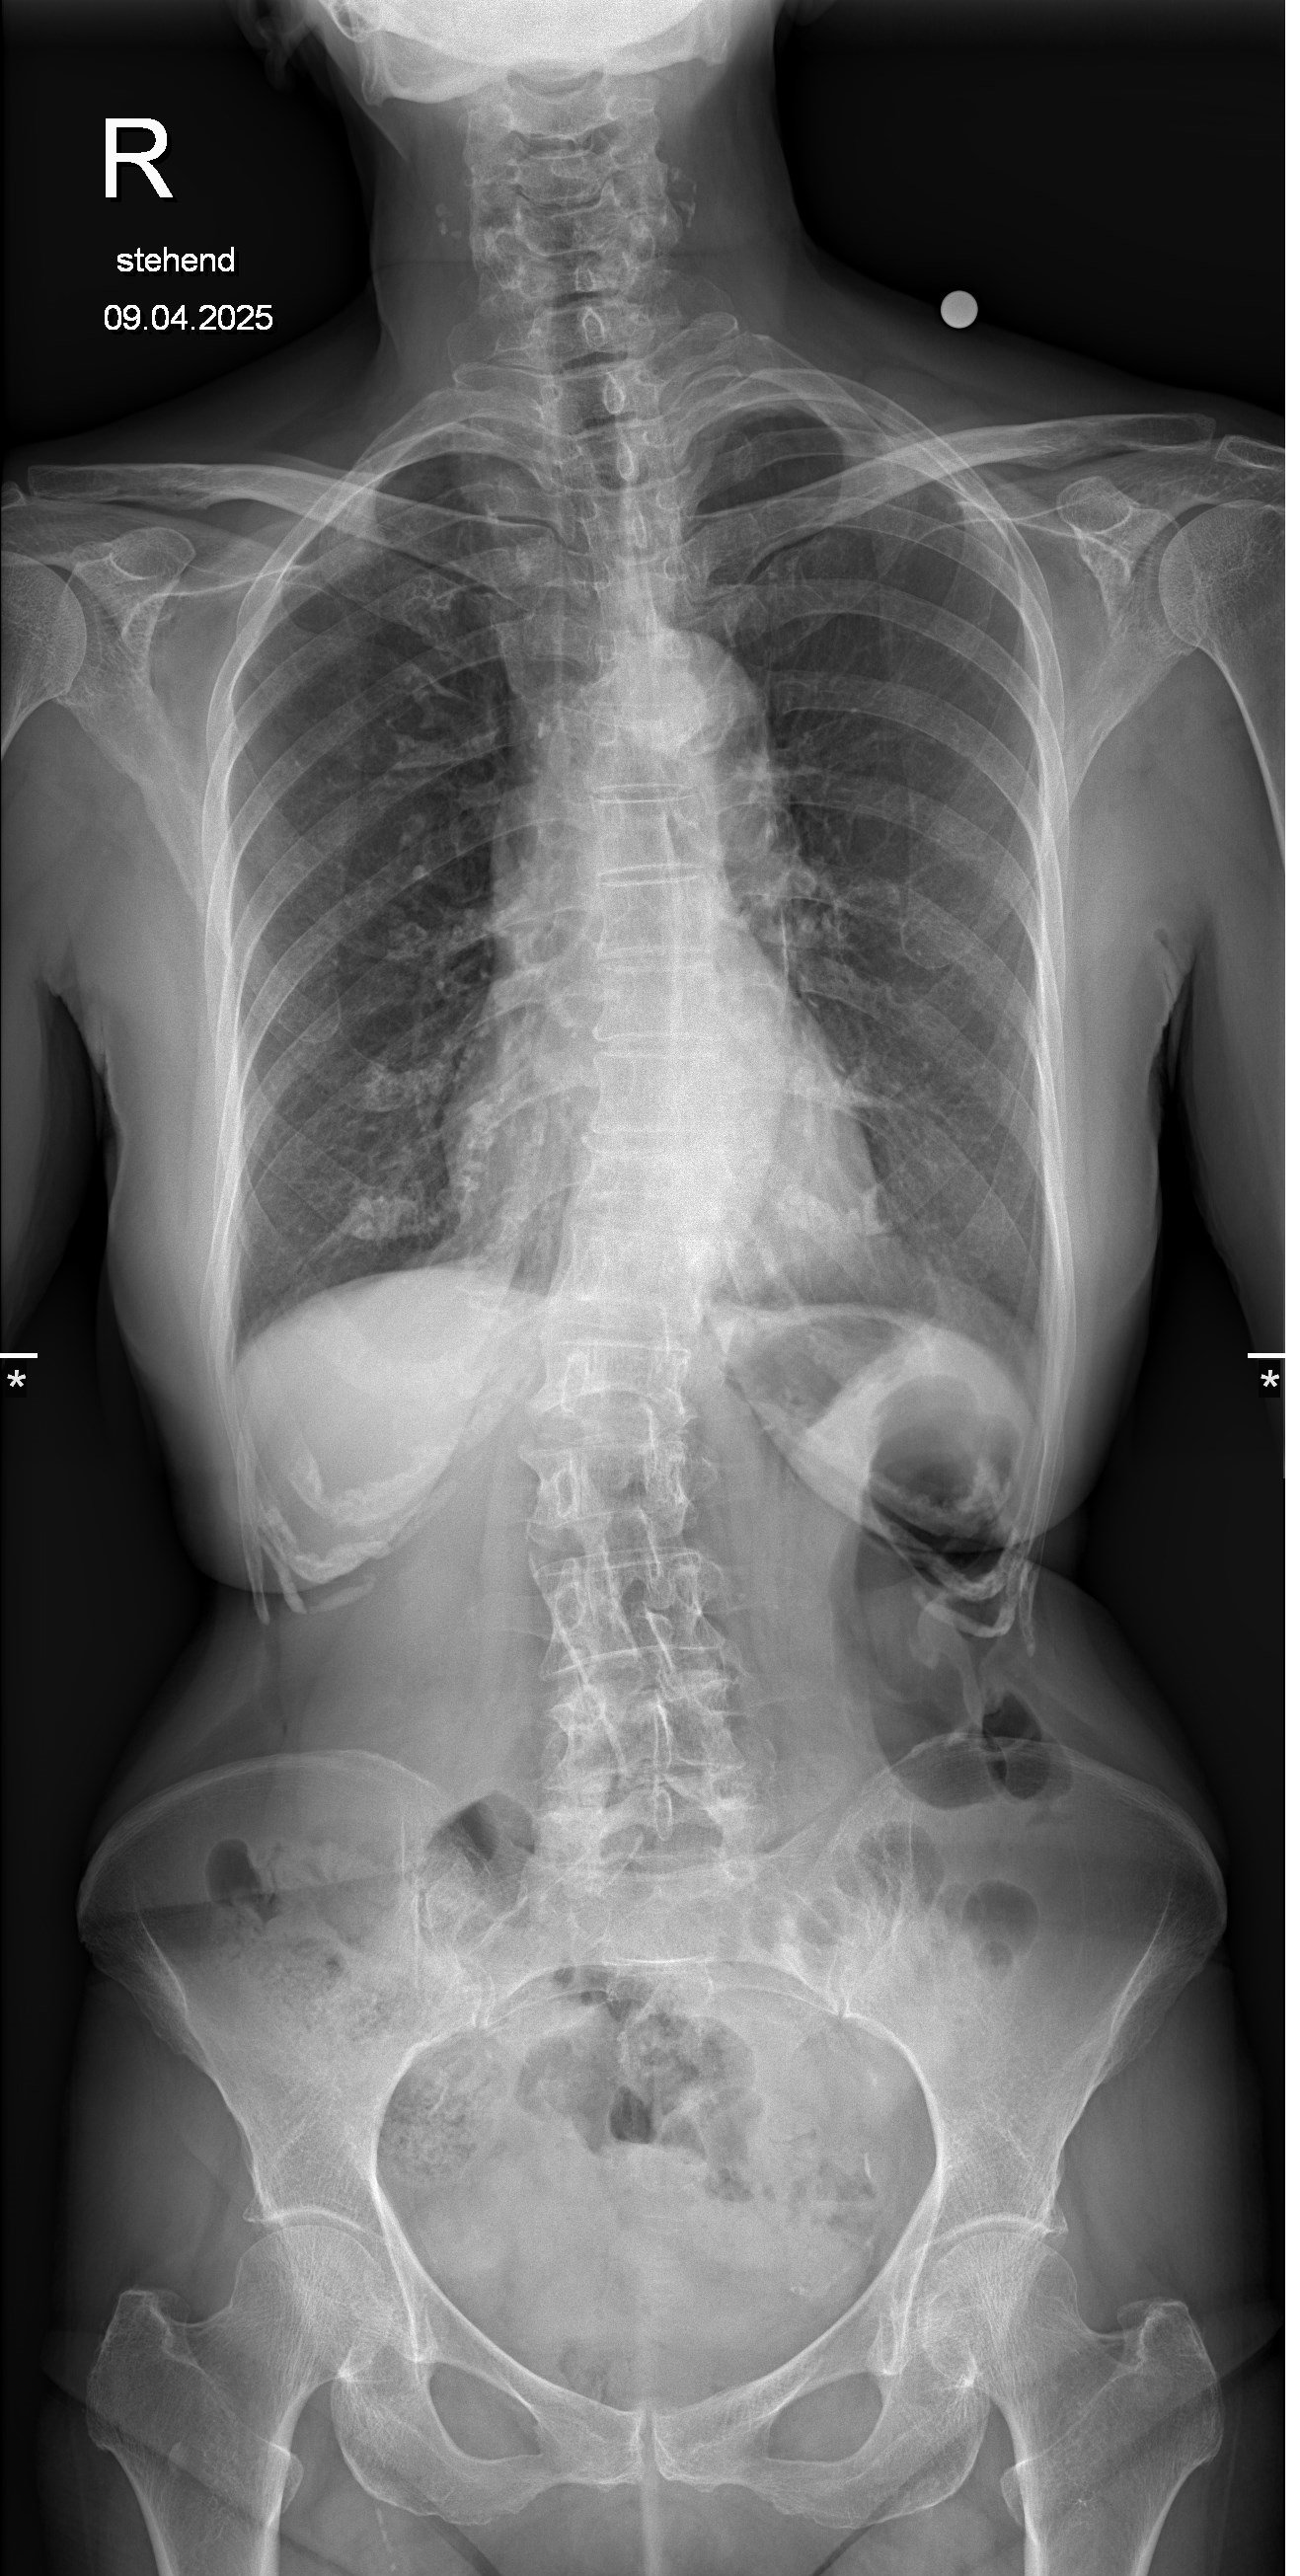

Voit nähdä kuvassa alhaalla muodonmuutoksen ......

Hänellä on useita murtuneita luita ja harvinainen Takayasun oireyhtymä (jota kutsutaan myös Takayasun valtimotulehdukseksi) on harvinainen, krooninen tulehdussairaus, joka vaikuttaa ensisijaisesti suuriin verisuoniin, erityisesti aorttaan ja sen suuriin haaroihin.

🔹 Takayasun arteriitti, harvinainen ja kivulias sairaus, joka tulehduttaa hänen suurimmat valtimonsa ja rajoittaa veren virtausta elintärkeisiin elimiin.

🔹 Osteoporoosi, joka on heikentänyt hänen luitaan niin paljon, että pienetkin liikkeet voivat aiheuttaa kovaa kipua tai murtumia.